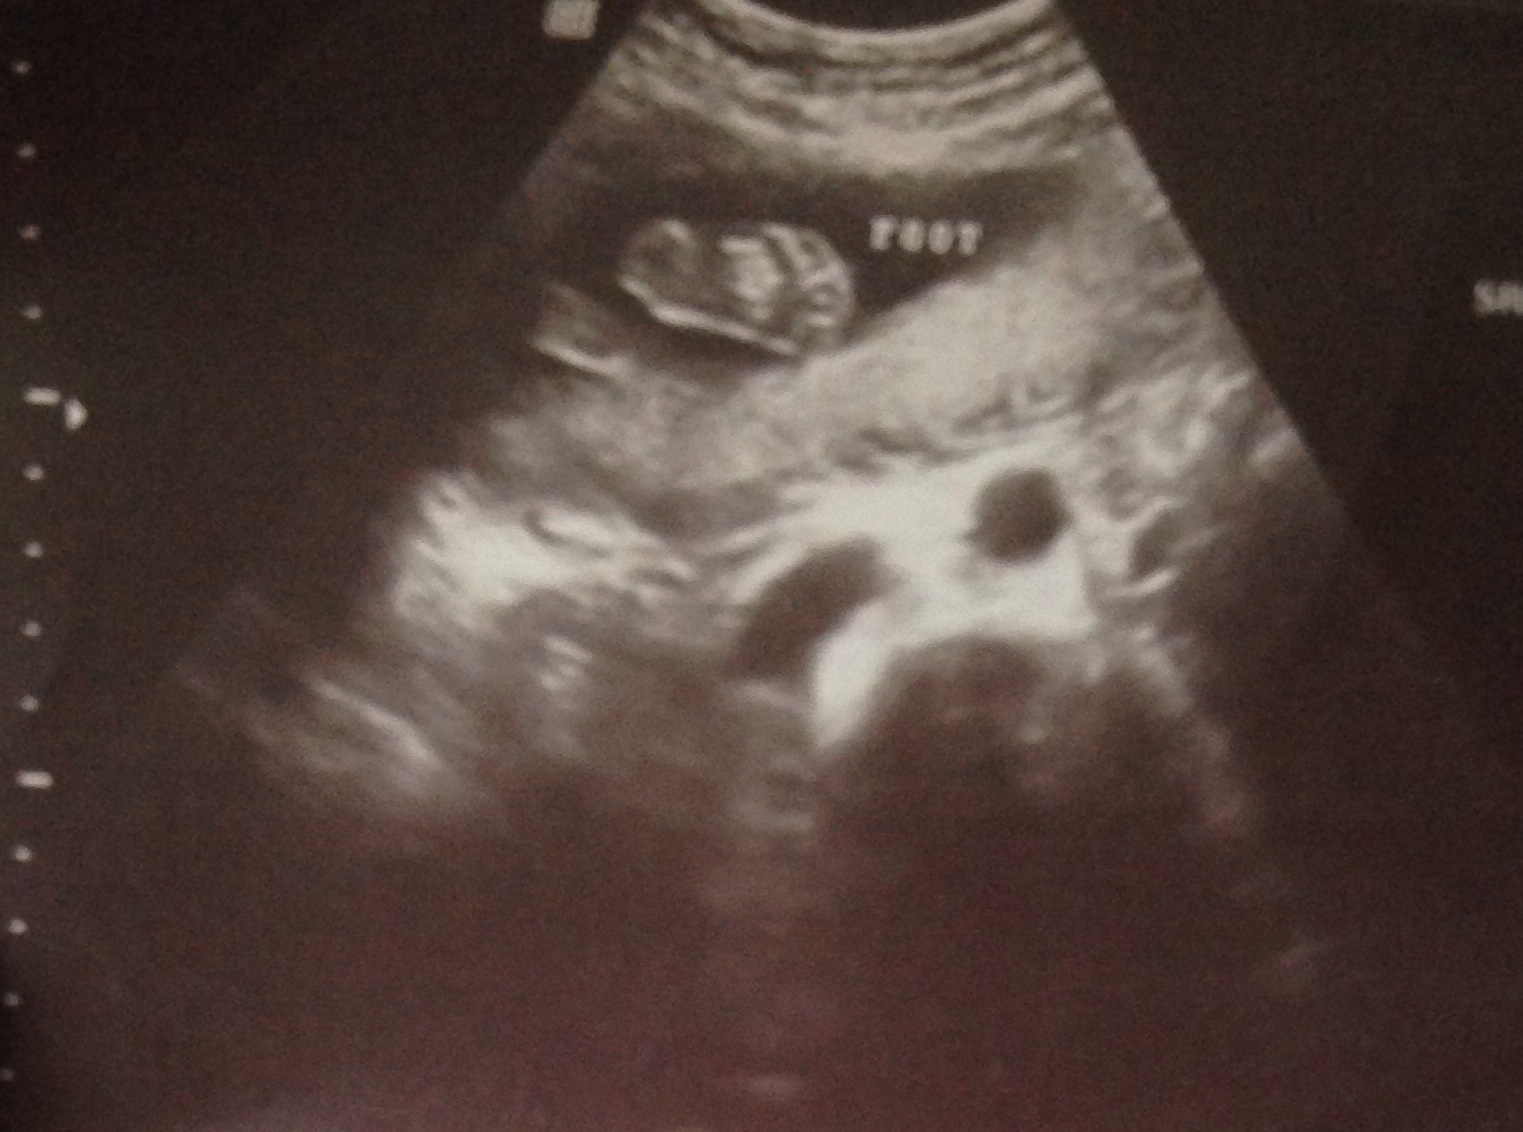

Also, from our u/s 3 weeks ago. Love the little foot that has been kicking me a lot more now!

I love the u/s of him crossing his feet!